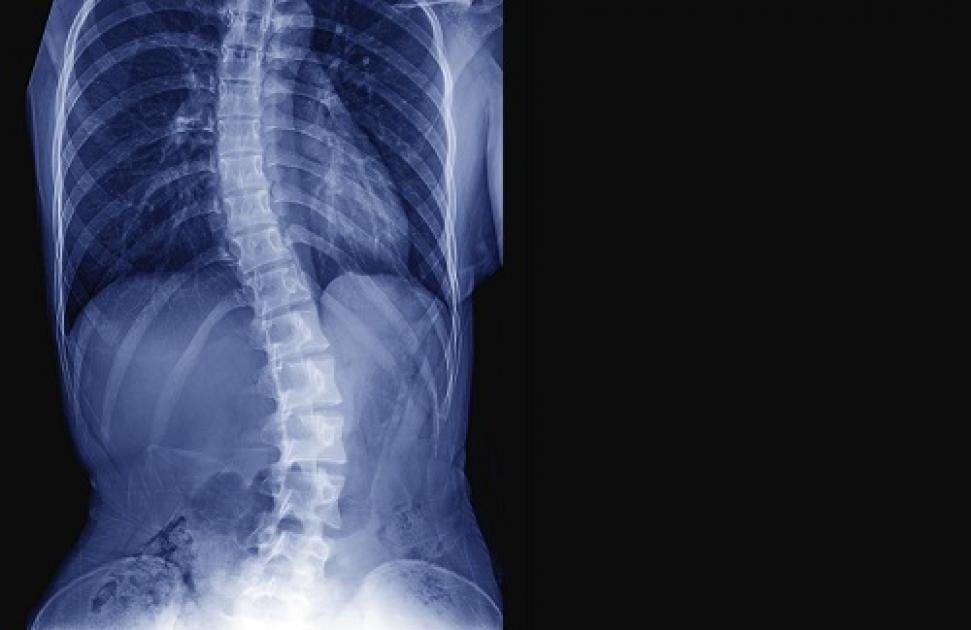

La scoliose idiopathique concernerait, en France, entre 0,5 et 2 % des 8-15 ans, principalement les filles, pour lesquelles l’incidence est 8 fois plus élevée que chez les garçons, estime la Cnam. De manière plus rare, des scolioses peuvent également apparaître à la suite d’une maladie neuromusculaire ou osseuse.

En cas de détection d’une scoliose, l’objectif est de limiter l’aggravation de la déformation du rachis, notamment chez les enfants et les adolescents : elle doit être la plus modérée possible à la fin de la croissance. Pour cela, les traitements de kinésithérapie et d’orthopédie, le port d’un corset et, pour les cas les plus sévères, un traitement chirurgical de la scoliose peuvent être envisagés.

Pour que son évolution soit favorable, il est primordial de la dépister le plus tôt possible. Dans la plupart des cas, la recherche d’une scoliose en médecine générale, en kinésithérapie ou en podologie ne présente pas de difficulté particulière, et repose notamment sur le repérage d’une gibbosité en flexion antérieure. "Mais ce n’est pas toujours évident, souligne Mélinda Tapie, kinésithérapeute au Pôle de santé Ouest Anjou. À cet âge, les préadolescents et adolescents ont souvent tendance à cacher leur corps, et il devient difficile pour les parents de les observer." Même en consultation de routine, si le patient n’est pas amené à se dénuder, une scoliose peut passer inaperçue. "C’est pourtant une période critique pour la scoliose, car la croissance est rapide, et pour intervenir, il est primordial d’avoir ce regard", précise la kiné.